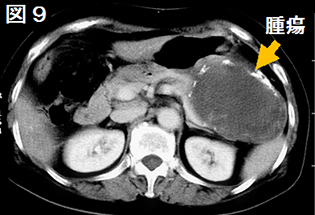

膵管内乳頭粘液性腫瘍(IPMN:図8)は、膵液の通り道である膵管の上皮から発生し、粘液を多く産生する腫瘍です。高齢男性の膵頭部に好発します。発生する部位が中心部の太い膵管からできるか、枝の膵管から発生するかで分類されており、それらの悪性度が異なります。膵臓の中心を走る太い膵管からできる場合は「主膵管型」と言われ、がんになる可能性が高いため手術適応となります。また、その膵管につながる枝の膵管から発生した場合は「分枝膵管型」と言われ、袋の大きさや袋の中に見える腫瘍の大きさなどでがん化の可能性を考慮した上で、手術をするのか定期的に状態の変化を見ていくのかが決まります。また、両方が同時に存在する「混合型」というのもあります。この場合は、主膵管型が含まれますので、主膵管型に準じた治療を行います。検査や治療法は浸潤性膵管がんと同じですが、がんであっても膵管内にとどまっていることがあり、その場合は浸潤性膵管がんに比べ再発の可能性が極めて低くなり長期の予後が期待できます。一方、粘液性嚢胞性腫瘍(MCN:図9)は中年女性の膵体尾部に好発します。

図9 粘液性嚢胞性腫瘍

嚢胞の上皮下に卵巣様間質が存在することから、ほとんどすべてが女性です。良性から悪性までさまざまな段階の腫瘍が存在しますが、IPMNよりも悪性度が高く、嚢胞を越えて膵組織へ広がった場合は肝転移やリンパ節転移を起こすことがあり、浸潤性膵管がんと同様に予後不良となります。したがって、MCNと診断された時点で手術適応となることが多いです。IPMNやMCNに対する化学療法は浸潤性膵管がんに準じて行われておりますが、その効果についてはまだはっきりしておりません。治療選択に関しては「IPMN/MCN国際診療ガイドライン」が日本を中心に世界に先駆けて発表されております。早い段階で適切な治療方法の選択をすることで良好な予後が望める病期ですので、膵臓の嚢胞があると言われた場合は、診断から治療まで一貫して行っている当科への受診をお勧めいたします。